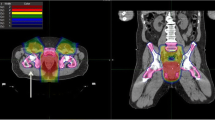

Three new clinical target volumes were defined and extended by 1 cm to create the PTVs. First, the original CTV was reduced by 1, 2 and 3 cm (longitudinal) and if necessary, adjusted to bones and vessels. By using 1 cm safety margin of these CTVs, PTVs were defined for each patient: The standard PTV minus 1 cm cranially (PTV-1), the standard PTV minus 2 cm cranially (PTV-2) and the standard PTV minus 3 cm cranially (PTV-3) (Fig. 1). The goal was to keep the shortest PTV (PTV-3) at least 2 cm above the last macroscopically visible primary tumor or lymph node metastases on MRI scan.

The mean volumes of the PTV0, PTV-1, PTV-2 and PTV-3 were 1524 cc, 1466 cc, 1366 cc and 1255 cc. This is a reduction of just 18% from PTV0 to PTV-3. The dose coverage of all PTVs was performed accurately, which resulted in identical mean Dmean, mean Dmedian and mean Dmax. For the bone marrow, the small bowel loops and the peritoneal space nearly all absolute and relative dose parameters were significantly reduced for the new PTVs (PTV-1, PTV-2, PTV-3) compared to PTV0 (Tables 2 and 3, Fig. 2).

Change in dose distribution after a target volume reduction of 3 cm. Protection of OARs. Differences in dose distribution (colour-wash) of the original bPTV (left) and the cranial 3 cm reduced PTV (3 cm, right). Especially the low and middle dose range covering less volume of the peritoneal space (green shape) and the bladder (yellow shape)